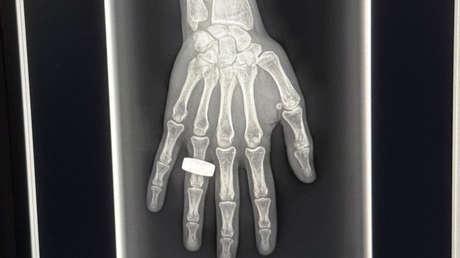

Chun Wang, comandante de la misión privada Fram2, publicó este miércoles la primera imagen de rayos X de un humano obtenida en el espacio, un logro histórico que "abrirá las puertas a una amplia gama de aplicaciones clínicas, de investigación e ingeniería".

La obtención de las imágenes radiográficas en órbita forma parte del experimento SpaceXray que, según el servicio de prensa de Fram2, tiene como objetivo probar "el primer sistema de rayos X jamás lanzado al espacio" para demostrar principalmente su capacidad de "visualizar estructuras orgánicas como huesos, pulmones y dientes".